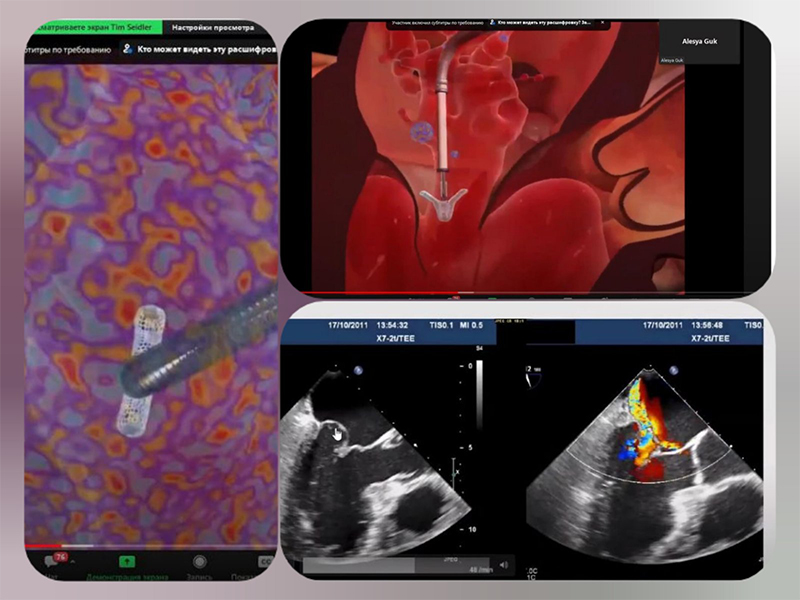

Тім Зідлер, старший консультант та заступник директора клініки Серця Медичного Університету Геттінгену, прочитав лекцію «Клапанна хвороба серця», яка викликала неабиякий інтерес.